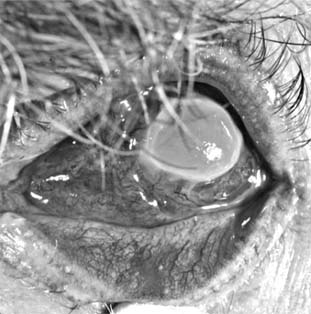

Pseudomonas corneal ulcer begins as a gray or yellow infiltrate at the site of a break in the corneal epithelium (Figure 6-2). Severe pain usually accompanies it. The lesion tends to spread rapidly in all directions because of the proteolytic enzymes produced by the organisms. Although superficial at first, the ulcer may affect the entire cornea. There is often a large hypopyon that tends to increase in size as the ulcer progresses. The infiltrate and exudate may have a bluish-green color. This is due to a pigment produced by the organism and is pathognomonic of P aeruginosa infection.

Figure 6-2

Figure 6-2: Pseudomonsa ulcer related to 24-hour contact lens wear.